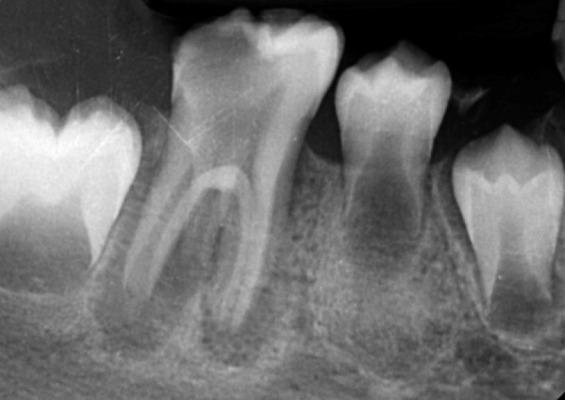

Regenerative endodontic procedures (REPs) have emerged as a biologically driven approach for managing immature teeth with necrotic pulp and open apices, providing an alternative to traditional apexification techniques. This case report describes the successful treatment of a three-rooted immature mandibular first molar with necrotic pulp and chronic apical periodontitis in a 9-year-old patient using REPs. The treatment followed the guidelines set by the American Association of Endodontists and utilized a two-visit protocol. Concentrated growth factor (CGF) was employed as a biological scaffold in the root canals, while calcium-enriched mixture (CEM) cement was used for the coronal seal. Radiographic evaluations conducted at 6, 12, and 15 months revealed progressive periapical healing, significant root elongation, increased thickness of the root walls, and partial apical closure. Clinically, the patient remained asymptomatic during all follow-ups. This case highlights the potential of CGF and CEM cement-enhanced REPs to promote continued root development and achieve predictable outcomes in immature teeth with necrotic pulps, offering a biologically based alternative to conventional apexification.

再生牙髓治疗程序(REPs)已成为一种以生物学为驱动的方法,用于处理牙髓坏死且根尖孔开放的未成熟牙齿,为传统根尖诱导成形技术提供了一种替代方案。本病例报告描述了一名9岁患者的下颌第一恒磨牙三根未成熟牙,患有牙髓坏死和慢性根尖周炎,采用REPs成功治疗的过程。治疗遵循美国牙髓病学家协会制定的指南,并采用了两次就诊方案。浓缩生长因子(CGF)被用作根管内的生物支架,而富钙混合物(CEM)水泥用于冠部封闭。在6个月、12个月和15个月时进行的影像学评估显示根尖周逐渐愈合、牙根显著伸长、根壁厚度增加以及根尖部分闭合。临床上,患者在所有随访期间均无症状。本病例突出了CGF和CEM水泥增强的REPs在促进未成熟牙髓坏死牙齿持续牙根发育并实现可预测结果方面的潜力,为传统根尖诱导成形提供了一种基于生物学的替代方法。